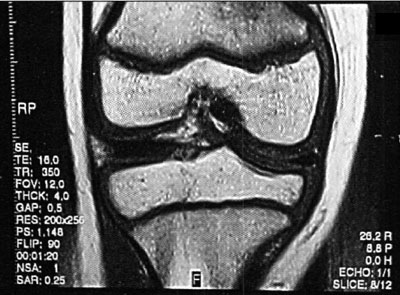

Foto 5: Lesión o.C. visualizada en RMN

La clasificación a partir de imágenes radiológicas mostró un coeficiente de correlación de Spearman de 0,77 (p=0,001) con respecto a la clasificación realizada a partir de imágenes tomográficas, en tanto que el mismo coeficiente entre las imágenes de TAC y RMN fue de 1 (p < 0,001). Esto implicaría una alta correlación entre la clasificación de TAC y RMN mientras que existiría una menor correlación entre Rx y TAC. En relación a los hallazgos de resonancia magnética, 12 pacientes (29,3 %) presentaron un GI, seis pacientes (14,6 %) presentaron un Gila, siete pacientes (17,1 %) un Glib, trece pacientes (31,7 %) un GIII y tres pacientes (7,31 %) un G IV. (fotos 6 a 10) Dieciocho pacientes (43,9%) fueron tratados en forma conservadora y 23 pacientes(56,1%0) fueron tratados en forma quirúrgica. (Ver tabla 4)